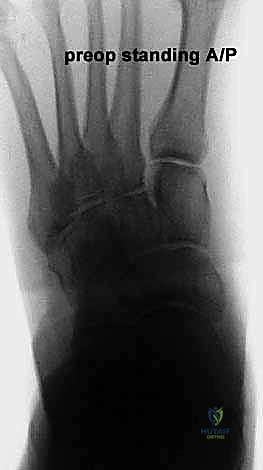

* الأشعة السينية (X-rays) مع تحمل الوزن: ضرورية لتقييم درجة انهيار القوس وزوايا العظام (مثل زاوية تالونافيكولار Meary's Angle).